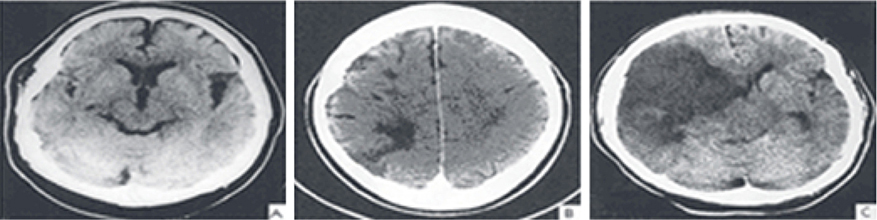

뇌경색은 병에 걸려 후 얼마나 빨리 치료를 착수하는지에 따라 병의 증세가 결심되기도 합니다. 증상이 발생하면 아주많이 빨리 병원을 가서 초급성기 치료를 받아야합니다. 급성기 치료 후에는 이유가 되는 것에 따라 재발 방지를 위한 치료를 하게 되며 후유증에 대한 재활치료도 가능한 한 빨리 실행하는는게게 좋바람직해요. 증상이 처음 나타난 후 4~5시간이 경과하지 않으신다면 주사 제제를 통한 혈전용해술을 시도해 볼 수 있어요. 그리고 24시간이 경과하지 않았고 대뇌혈관이 막힌 것을 확인했으면 막힌 혈관에 대하여서 스텐트 투여술과 같은 기계적 재개통술을 시도할 수 있습니다.

뇌경색 후유증은 제대로 걷지 못하며, 말을 잘 못하였거나, 나의 의지와는 다르게 출현하는 문제점들이 일어날 있다고 합니다. 그렇기에 뇌경색 초기증상이 발견될 시 날쌔게 조치를 해야 후유증이 희박합니다 뇌경색이 오면 후유증이 남는 것이 기본이며 일주일 안으로 나타나게 된다고 해요. 이 기간이 지나도 병의 증세가 없다고 하나 서서히 회복이 되는 단계에 있다고 보시면 되기도 합니다 뇌경색 후유증은 3개월에서 6개월 사이에 서서히 회복 될 수 있습니다. 치료가 늦어져서 뇌경색 후유증이 절박하게 자리잡게 된다면 일상생활이 어려울 정도로 사람의 몸에 이상이 있는 상태가 지켜질 수 있어요.